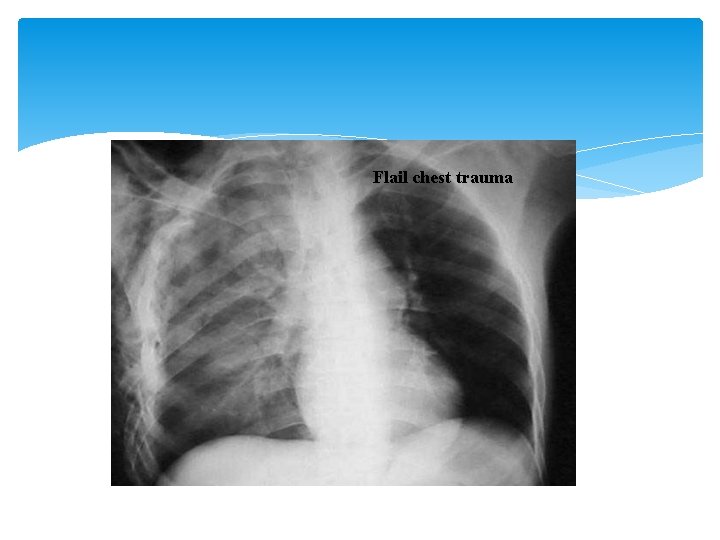

Flail Chest v Caused by Blunt trauma http: //www. youtube. com/watch? v=u. JHf. X 1 RFk. F 0

Flail chest trauma